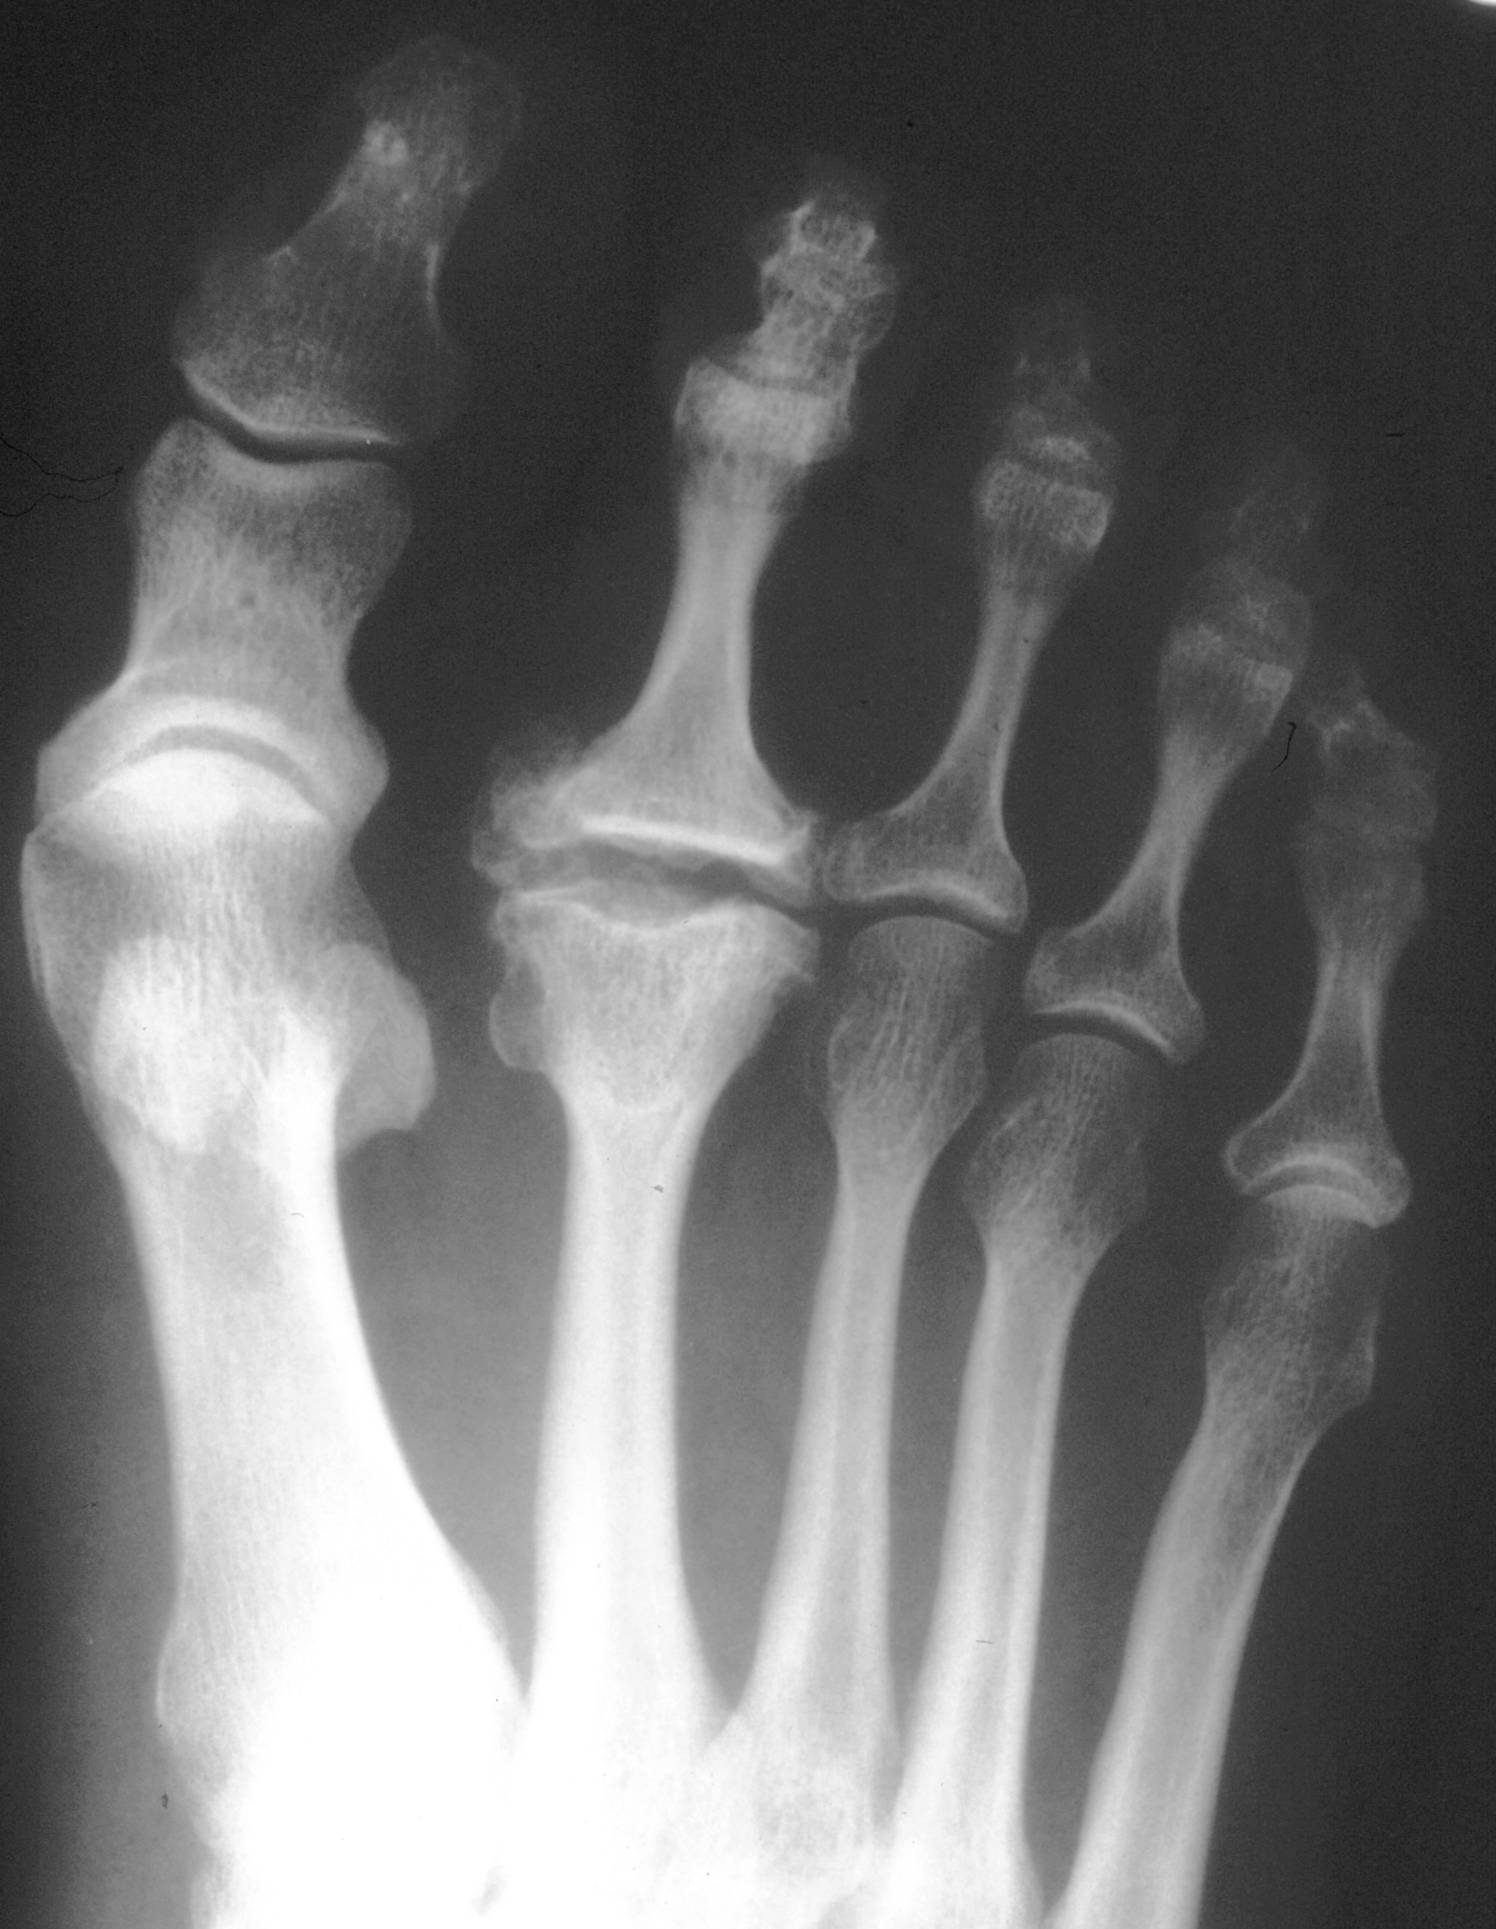

Im Frühstadium liegt oft eine schmerzhaft eingeschränkte Beweglichkeit, vor allem für die Dorsalextension, vor. Ein axialer Stauchungsschmerz deutet auf ein intraartikuläres Geschehen möglicherweise in Kombination mit einer Synovitis hin. Die Umgebung des Gelenks kann etwas überwärmt sein. Im Spätstadium kann der dorsale Mittelfußkopf aufgetrieben sein, so dass eine knöcherne Auftreibung imponiert (Abb. 1). Korrespondierend kann sich eine Metatarsalgie entwickeln. Röntgenologisch imponiert eine dorsal betonte Destruktion des Mittelfußkopfs, die von ausladenden Osteophyten und einer erheblichen morphologischen Formstörung des Mittelfußkopfs begleitet sein kann.

Abb. 1.

Ausladende Osteophyten mit Formstörung des Mittelfußkopfs als radiologisches Zeichen des Morbus Freiberg-Köhler.